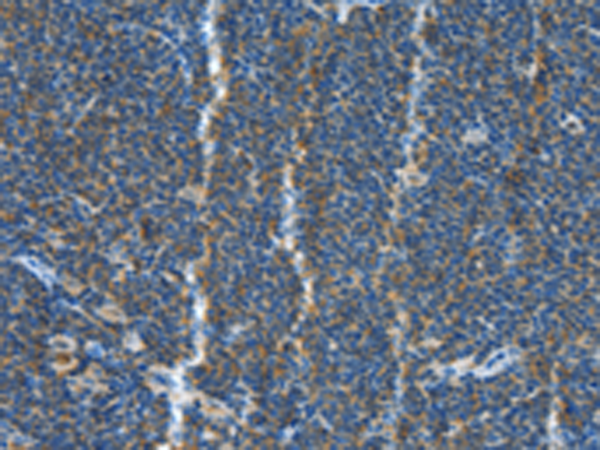

分类: 科研抗体货号: P07127别名: DTL; BAFF; BLYS; CD257; TALL1; THANK; ZTNF4; TALL-1; TNFSF20应用: IHC反应种属: Human